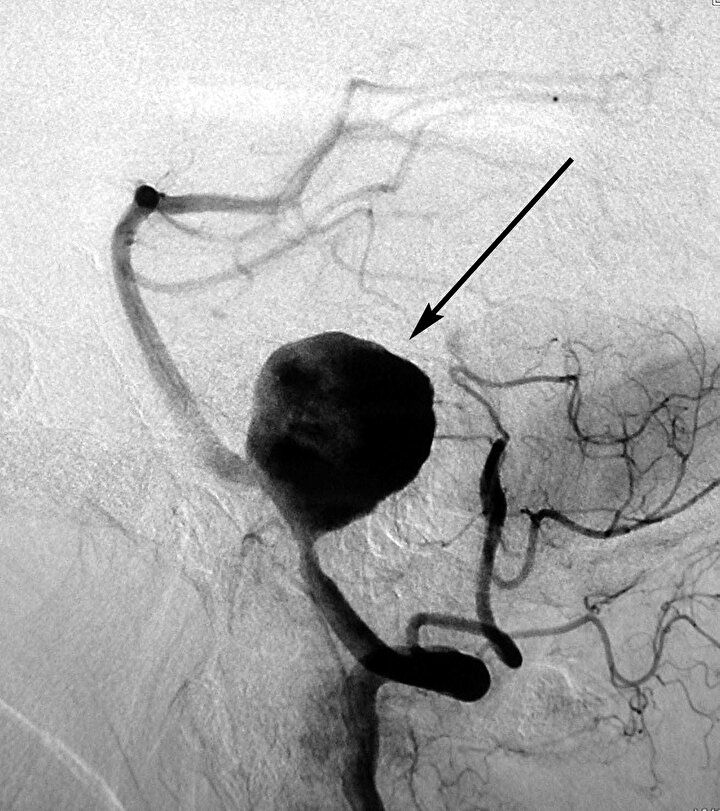

Tam 4 gün sonra gelen sonuçlarda dalak arterinde anevrizma olduğunu öğrenen genç anne hayatının şokunu yaşadı.

Oldukça nadir görülen bu durum Blackburn'ün moralini bozdu. Çünkü patlaması halinde üçte bir oranında ölüm riski taşıyordu. Dahası, ek testlerde de 2 anevrizması olduğu belirlendi.

Anevrizmaların konumu dolayısıyla doktorlar, genç kadına dalağının alınması gerektiğini söyledi.